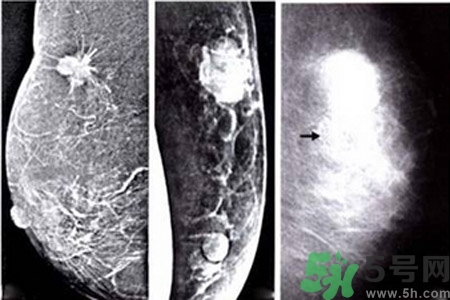

鈣化形態(tài)對(duì)辨別病變的良惡性有較大的意義,在觀察中發(fā)現(xiàn)。

顆粒狀、蛋殼狀、不規(guī)則團(tuán)塊狀及軌道狀鈣化多發(fā)生于良性病變。

針尖狀、小桿狀、分叉狀及泥沙樣鈣化多發(fā)生于惡性病變,鈣化的形式多樣、大小差異很大時(shí),惡性的可能性越大,單純出現(xiàn)一種形態(tài)的鈣化時(shí),成簇的針尖狀、分叉狀鈣化,對(duì)診斷惡性病變的意義較大。而單純出現(xiàn)泥沙樣鈣化,對(duì)病變的良惡性判別則比較困難。泥沙樣鈣化為不確定性鈣化,良惡性有重疊,但如果泥沙樣鈣化伴有其他鈣化形式,提示惡性病變。

了解鈣化部位應(yīng)強(qiáng)調(diào)多方位、多角度觀察。良性鈣化灶,多發(fā)生在纖維組織、脂肪、血管、大汗腺、皮膚等乳腺間質(zhì)內(nèi),乳腺實(shí)質(zhì)內(nèi)少見(jiàn)。惡性鈣化則多發(fā)生于乳腺實(shí)質(zhì)內(nèi),泥沙樣鈣化多發(fā)生在乳腺小葉腺泡內(nèi),小桿狀鈣化多發(fā)生在導(dǎo)管內(nèi),小叉狀鈣化則多位于末支小導(dǎo)管內(nèi)。

乳腺鈣化與腫塊的關(guān)系

鈣化可與腫塊并存,也可獨(dú)立存在;既可發(fā)生在病變內(nèi),也可獨(dú)立于腫塊之外。90%的導(dǎo)管原位癌是通過(guò)X線鉬靶照片發(fā)現(xiàn)的,且僅以乳腺內(nèi)鈣化作為惟一的表現(xiàn)形式。這是由于原位癌中央發(fā)生不規(guī)則壞死引起的鈣鹽在導(dǎo)管內(nèi)沉積或腫瘤細(xì)胞分泌而呈形態(tài)各異的的表現(xiàn)。